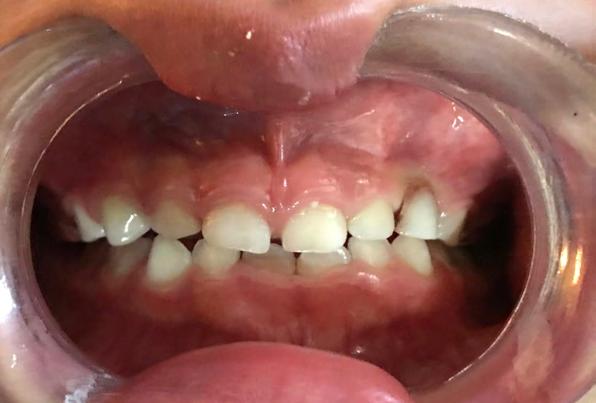

Se presenta una paciente de 52 años de edad, con tratamiento previo inconcluso. Es diagnosticada en el CESO con clase II esquelética, de crecimiento hiperdivergente, biotipo dolicofacial, con clase III canina y molar izquierda, clase III molar derecha, canino 13 retenido, mordida abierta anterior, ausencia de molares 26 y 46.

Se presenta una paciente de 52 años la cual menciona que ya había recibido un tratamiento previo de ortodoncia que quedó inconcluso, actualmente todavía tiene los braquetes de ese tratamiento. Pero ahora ella quiere iniciar un nuevo tratamiento en el CESO con el fin de mejorar su mordida. Es diagnostica con clase II esquelética, de crecimiento hiperdivergente, biotipo dolicofacial, clase III canina y molar izquierda,

clase III molar derecha, canino 13 retenido, mordida abierta, ausencia de los molares 26 y 46.

En las fotografías de inicio en la de frente (Figura 1) se observa la presencia de los brackets que todavía no han sido retirados y que son del tratamiento anterior, el perfil convexo.

Estudios de inicio intraorales

Las fotografías nos muestran en la Figura 2, la aparatología que se utilizó en el tratamiento que ella no terminó. La mordida abierta anterior de 1.5 mm, en la de frente las líneas medias no coincidentes, la clase III canina y molar izquierda, ausencia del canino 13 y del molar 46; en la Figura 3 el botón de Nance, algunos espacios en las arcadas.